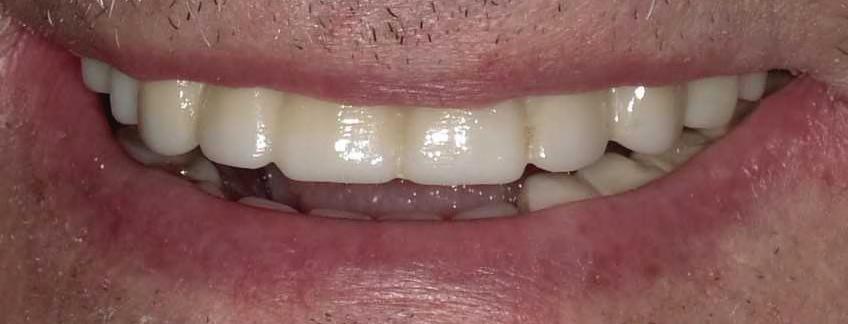

TeethXpress:

Restoring Smiles in a Day

“Technology has transformed dental care,” says Dr. Bryant—and his practice is proof. One of the most exciting advancements is TeethXpress, a same-day solution that replaces a full arch of teeth using four to six strategically placed implants and a fixed hybrid prosthesis.

Unlike removable dentures that can shift, cause discomfort, or require adhesives, TeethXpress offers a permanent, natural-looking solution that preserves jawbone health and allows patients to eat, speak, and smile with confidence—all in a single visit. For many, it’s a life-changing alternative to the insecurity and inconvenience of traditional dentures.

Patients walk in with missing or failing teeth and leave the same day with a secure, radiant smile. There’s no waiting period, no temporary dentures, and no dietary restrictions. Just immediate results and restored selfesteem.

Bryant Oral & Facial Surgery uses state-of-the-art Cone Beam Computed Tomography (CBCT) to make same-day dental implants possible. CBCT provides high-resolution, 3D imaging of the mouth and jaw, allowing for precise planning and customized implant placement. It’s this technology that enables the team to deliver such reliable, efficient, and comfortable results.

Using this data, the lab crafts custom prosthetics tailored to each patient— resulting in a fit that feels natural and looks flawless.

According to Dr. Bryant, ideal candidates for TeethXpress are patients who are just beginning to lose their teeth and have sufficient bone density. Those with medical conditions such as controlled diabetes, high blood pressure, or even certain autoimmune diseases may still qualify for the procedure. The key is a comprehensive, individualized evaluation.

Each treatment plan is uniquely designed to suit a patient’s dental history, health profile, and long-term goals. Even those who have been told they’re not candidates for traditional implants may find success with TeethXpress.

BEFORE AFTER